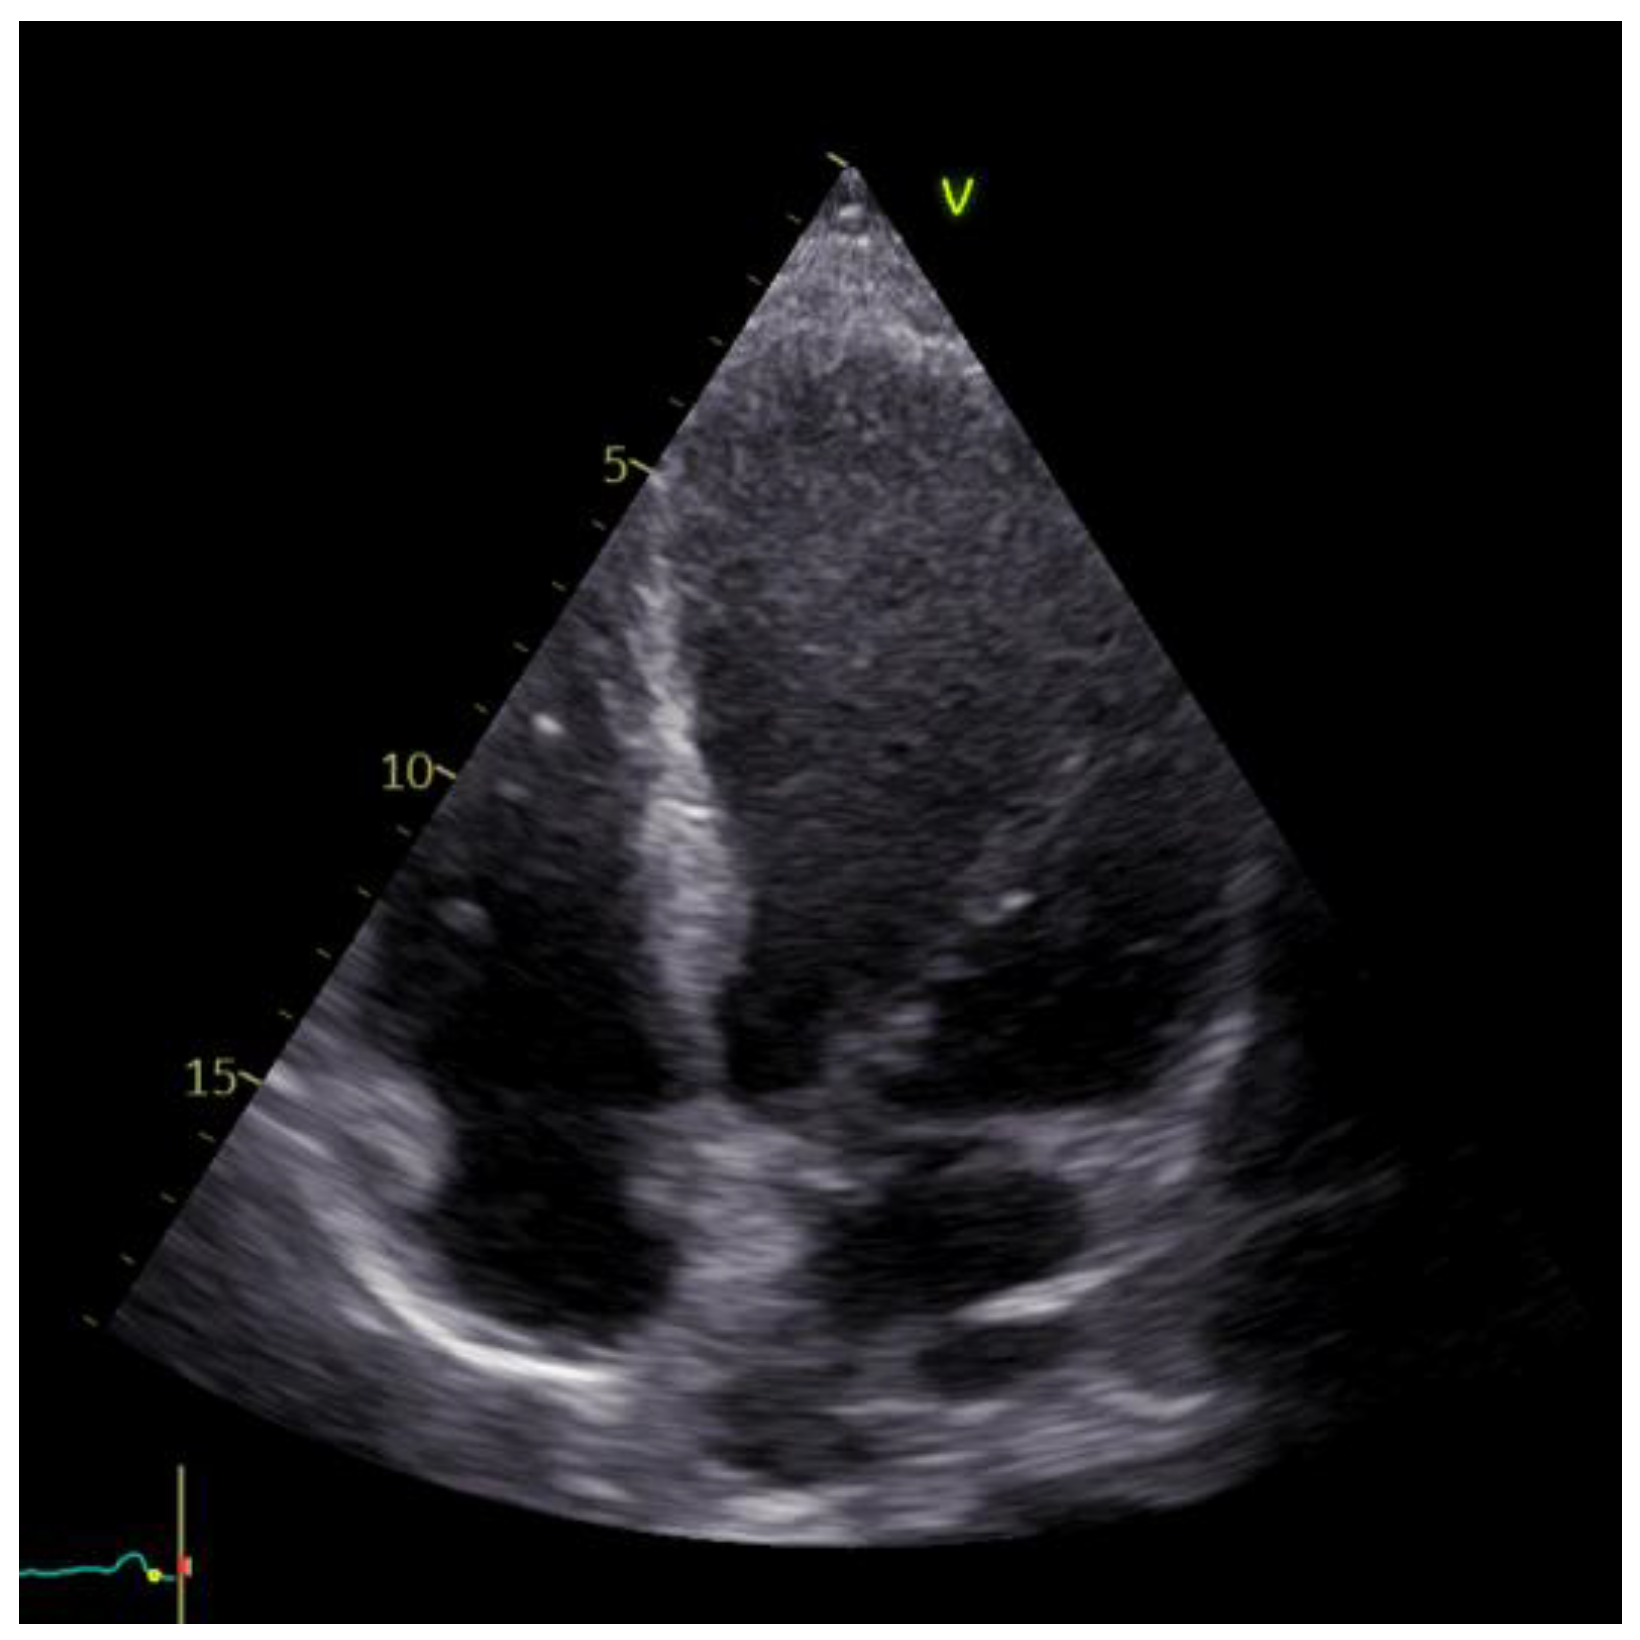

2. Detailed Case Description